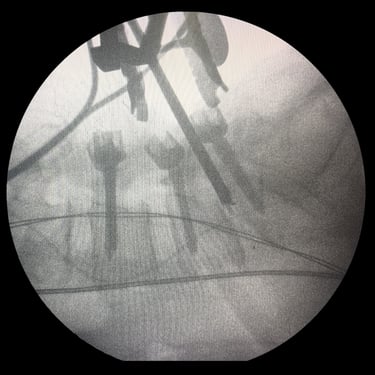

Columna lumbar inestable con listesis: tratamiento con artrodesis y tornillos transpediculares

La listesis lumbar ocurre cuando una vértebra se desplaza hacia adelante o hacia atrás respecto a la vértebra inferior, generando inestabilidad de la columna lumbar. Esta condición puede causar dolor lumbar crónico, compresión nerviosa, ciática, debilidad en las piernas o dificultad para caminar. Cuando el tratamiento conservador no es suficiente, la artrodesis lumbar con tornillos transpediculares es una alternativa quirúrgica eficaz. Este procedimiento permite fijar las vértebras afectadas mediante implantes que estabilizan la columna y favorecen la fusión ósea. Con técnicas modernas y abordajes mínimamente invasivos, se logra aliviar el dolor, mejorar la estabilidad vertebral y recuperar la función del paciente.